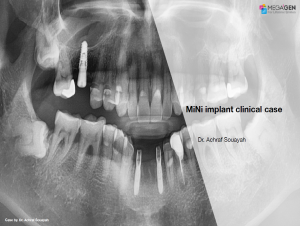

Dr. Achraf Souayah,Edentulous,Aesthetic zone,Maxillary Anterior,Maxillary Posterior,Mandibular Anterior,Mandibular Posterior,Guided surgery,Sinus Elevation,Immediate Placement,AnyRidge,Overdenture system,Meg-Rhein,MILA Kit,Clinical case